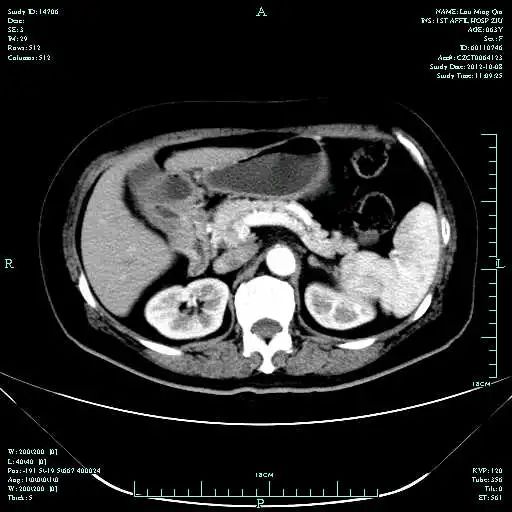

• CT示:肝转移

• MR示:

临床分期:cT4bN1M1,cStageⅣ

CT-T

CT-H1

MR-H1

影像学检查结果评估:cPD。